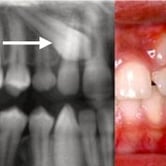

Dientes Supernumerarios

Los dientes supernumerarios son dientes adicionales que pueden aparecer en la boca y causar problemas de alineación o erupción de otros dientes.

Los pacientes pueden notar dientes adicionales en la boca, lo que puede causar apiñamiento o problemas estéticos.

El tratamiento incluye la extracción quirúrgica de los dientes supernumerarios.